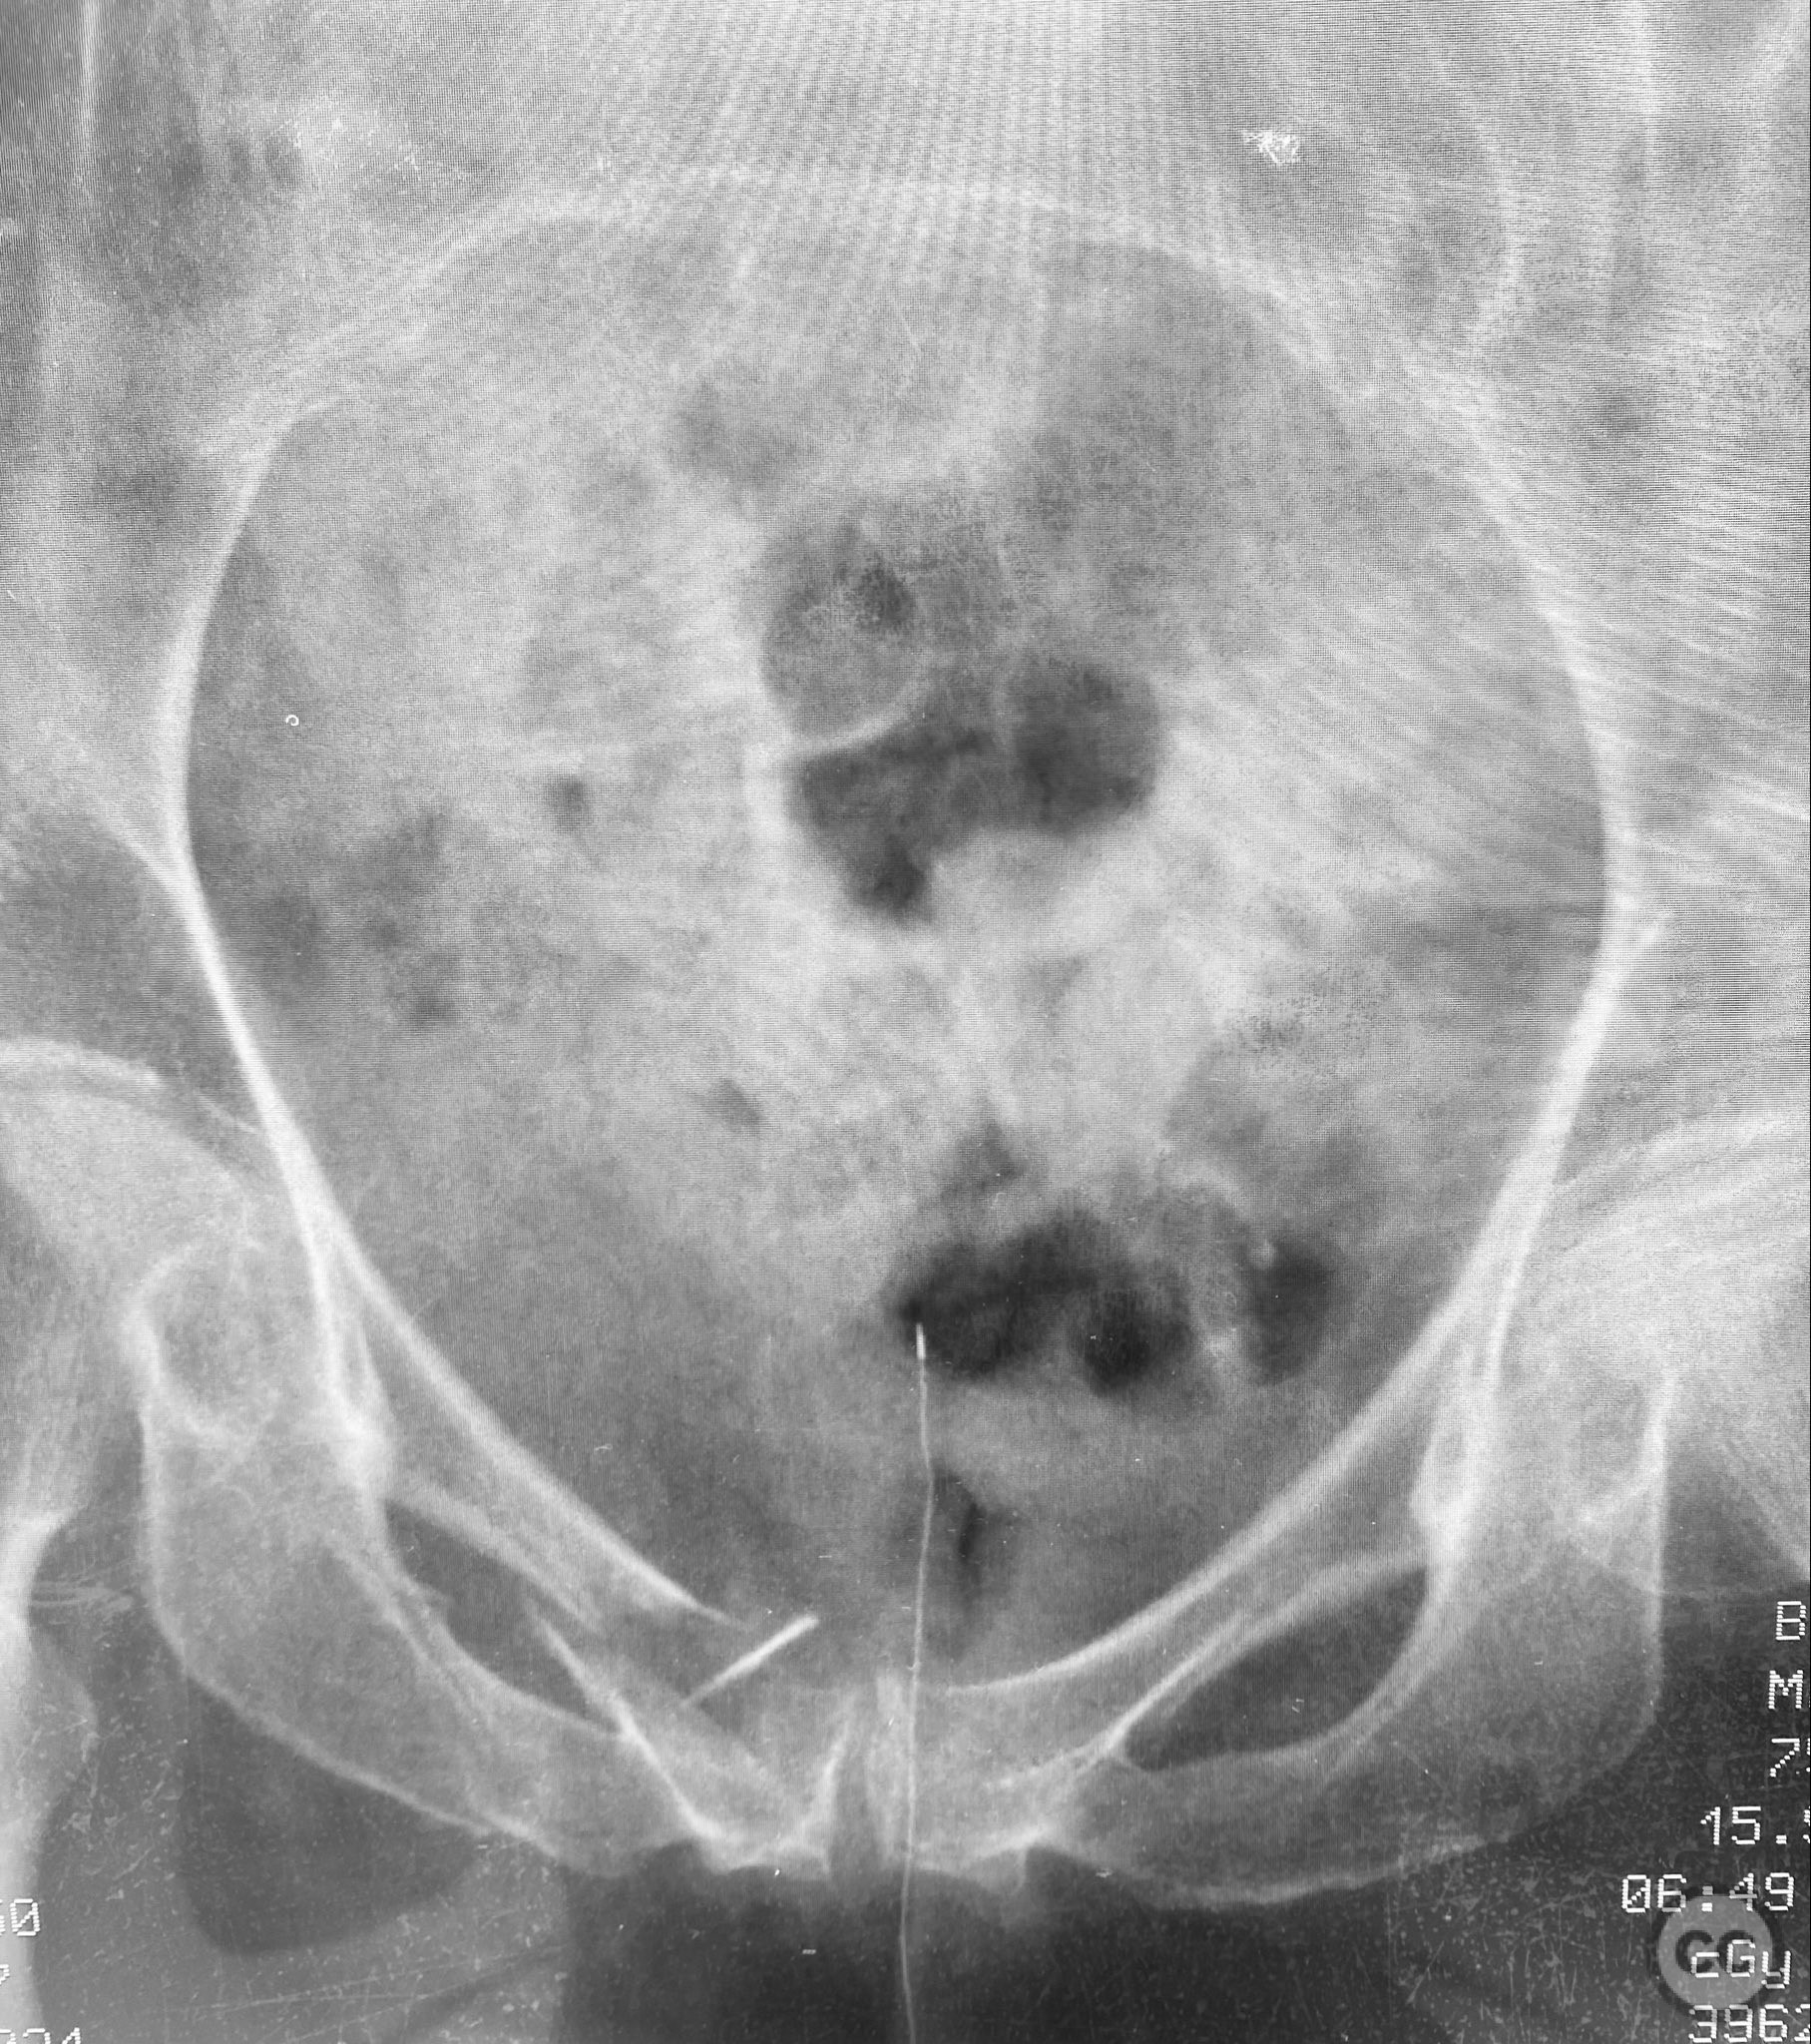

Clinical and radiological findings:  An 83-year-old previously healthy and active female sustained a fall resulting in severe pelvic pain and inability to mobilize. Clinical examination revealed marked pelvic tenderness and functional impairment. Radiological assessment, including examination under anesthesia with fluoroscopy (EUAF), demonstrated pelvic ring instability with minimal compression revealing the sites of instability, and rebound reduction upon release of compression. The injury is classified as an AO/OTA 61-B2.1 (lateral compression type I, incomplete posterior disruption).

Planning remarks:  The preoperative plan included percutaneous stabilization of the posterior pelvic ring using iliosacral (IS) screws placed in the upper sacral corridor. For anterior ring stabilization, a retrograde 4.5mm cortical blunt tip screw was planned for insertion along the superior pubic ramus isthmus, with implant size determined by the available bone corridor.